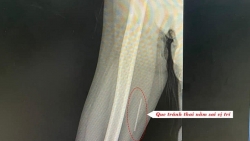

Hy hữu que tránh thai “đi lạc” trong cơ bắp tay

Bệnh viện Thanh Nhàn ghi nhận trường hợp bệnh nhân nữ 32 tuổi đi khám với triệu chứng đau khi cử động vùng cánh tay đã cấy que tránh thai.